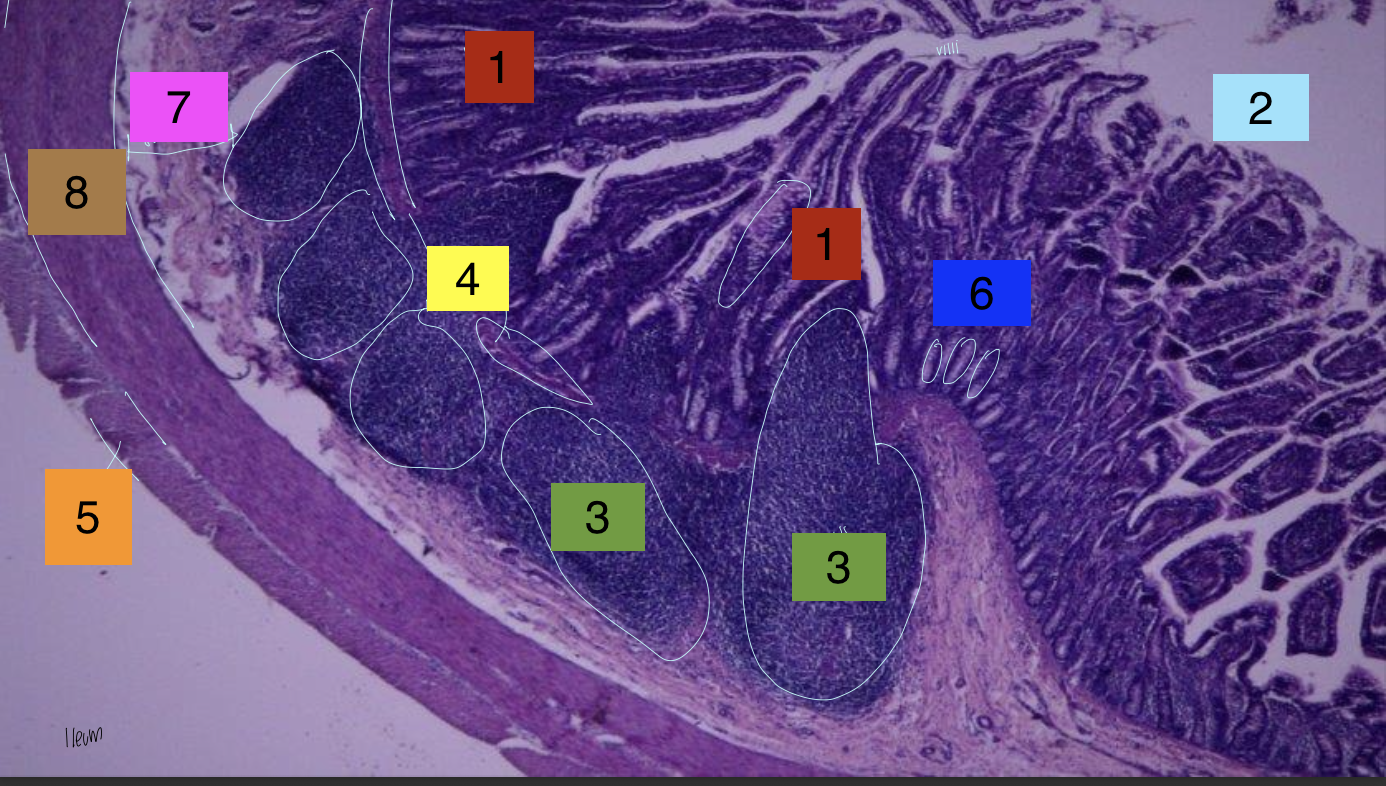

what is 1?

lamina propria

what is 2?

lumenÂ

what is 3?

peyer’s patches

what is 4?

lamina muscularis

what is 5?

longitudinal muscles

what is 6?

crypts

what is 7?

submuscosa

what is 8?

circular muscularis